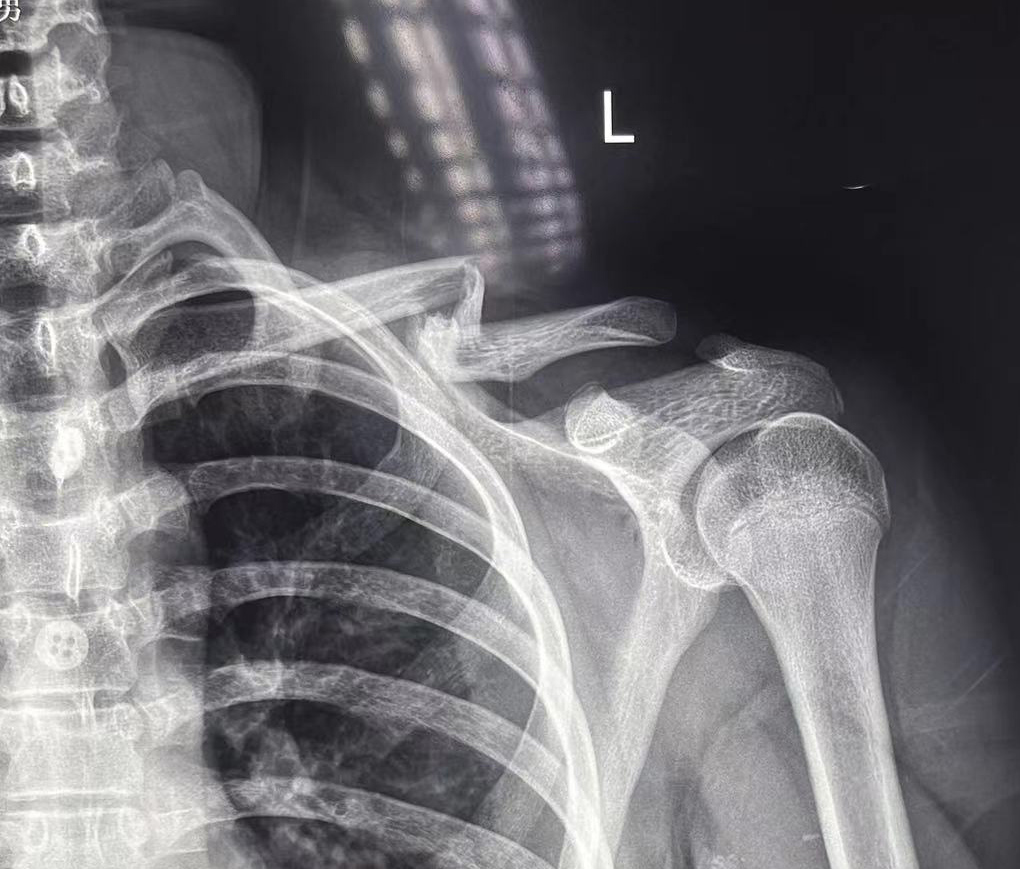

术前影像

来自甘肃省的小高于2024年8月25日在骑自行车时摔倒,当即出现左肩部疼痛、肿胀、活动受限的情况,在当地医院就诊,拍片显示“左锁骨中外1/3处粉碎骨折,断端重叠移位”,建议手术治疗。因各种顾虑,小高的父母不希望做手术。多方打听之后,一家人来到我院就诊,经门诊医师查体、阅片后以“左锁骨骨折”为诊断收入我院手法正骨二科。